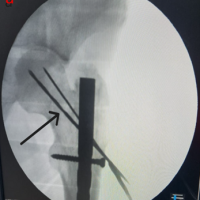

Surgical management of the non-union with an ORIF was performed under interscalene block with sedation. In a semi-sitting position, the non-union site was opened using a 10-cm longitudinal incision at the SC joint. The fracture site was exposed, edges curated, and hypertrophic callous was removed from the lateral sharp overriding edge (Fig. 3a), both edges have bleeding bone, approximated fixed by using left-sided lateral end clavicle locking plate (usually lateral portion could fit on the clavicle medial end) anteriorly with 4, 2.7 mm locking screw in medial fragment and 3, 3.5 mm cortical locking screw in the lateral fragment (Fig. 3b). Intraoperatively we found the purchase of 2 screws in the medial fragment unstable. Hence, we have augmented the fixation with a 3.5 mm recon plate superiorly with two simple screws in the medial fragment and two simple screws in the lateral fragment (Fig. 3c). A stable fixation was obtained without bridging the SC joint. The c-arm image is attached (Fig. 4).